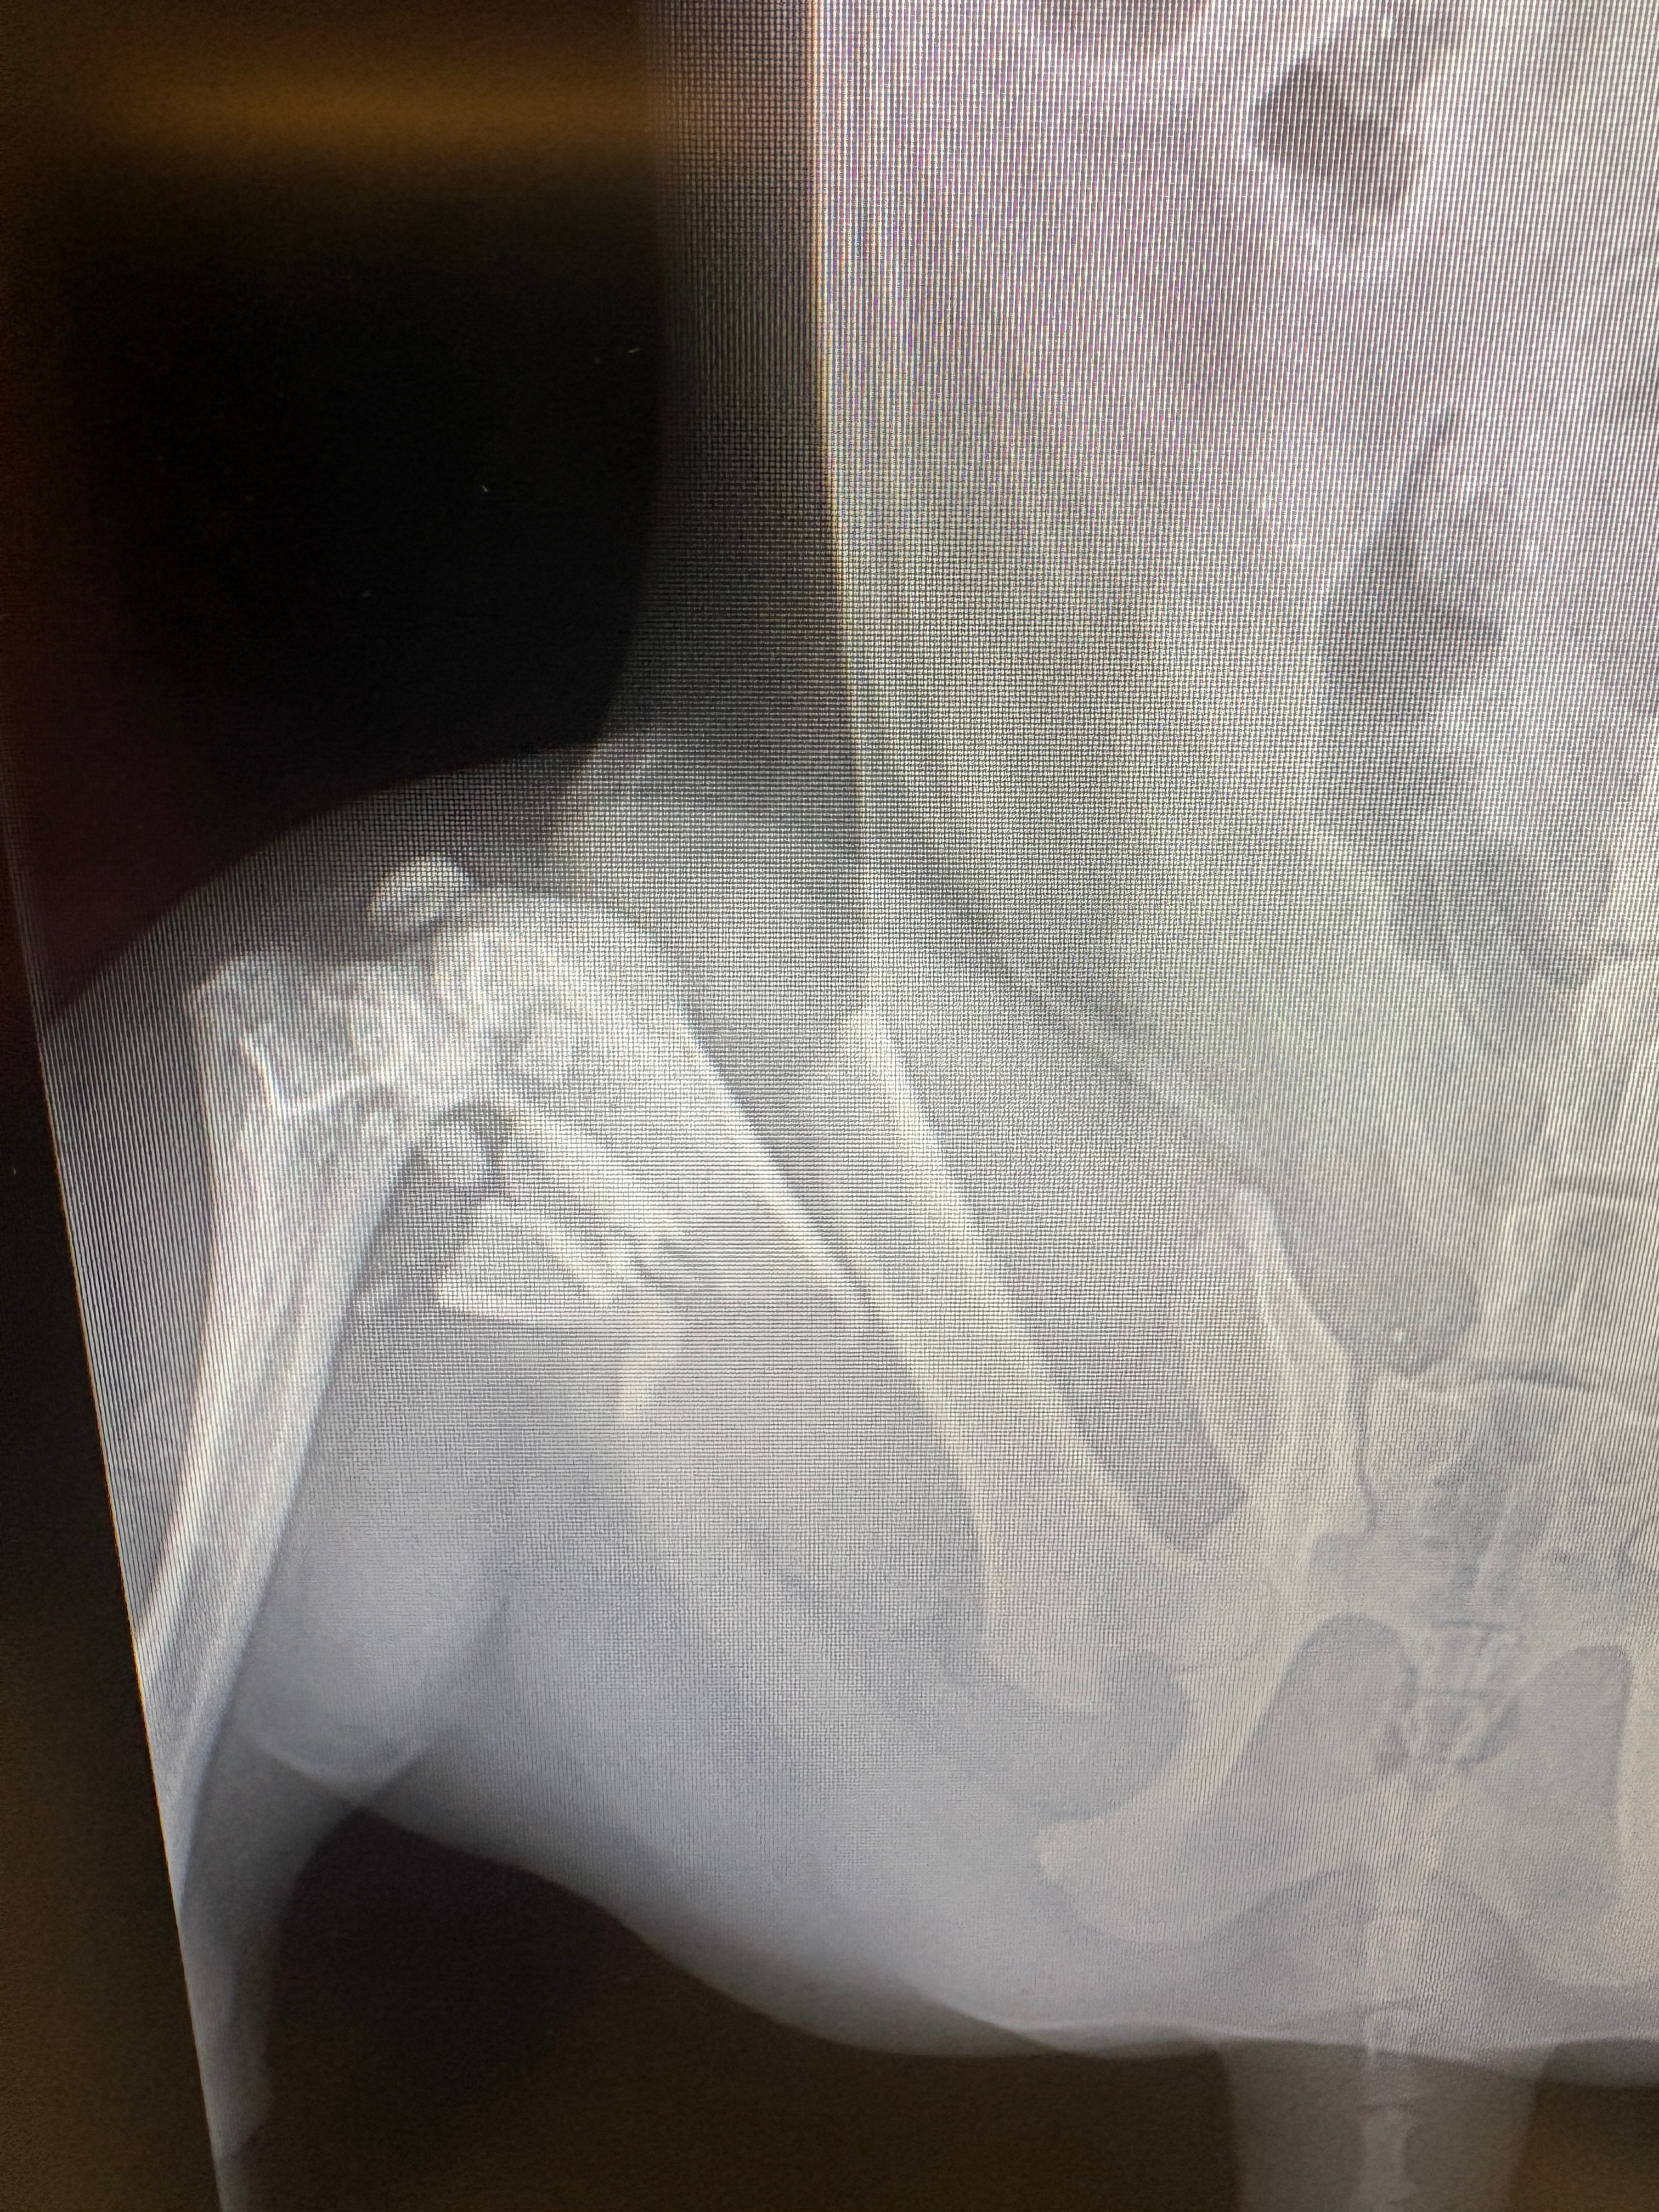

Our sweet girl now has a compound fractured femur and needs urgent surgery to save her leg and allow her to walk again. The veterinary team says the procedure will cost $10,894 — an amount far beyond what we can afford. Without this surgery, Aries faces unimaginable pain and the possibility of losing her leg.